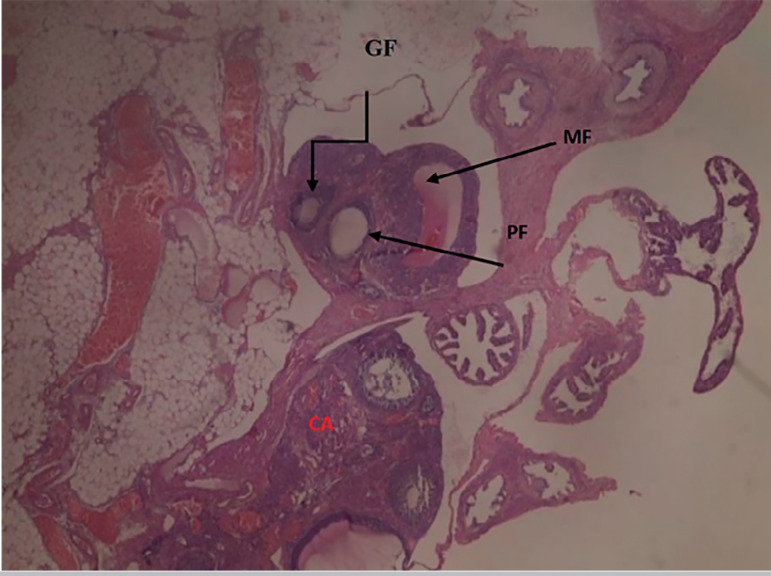

Results: The body weight of the rats showed a dose-dependent reduction (p<0.05), compared with the controls. Xylopia aethiopica seeds significantly (p<0.05) reversed the detrimental effects of Cadmium on LH and FSH. The histological analysis of the ovary showed significant improvement upon treatment with Xylopia aethiopica extract in a dose-dependent manner.